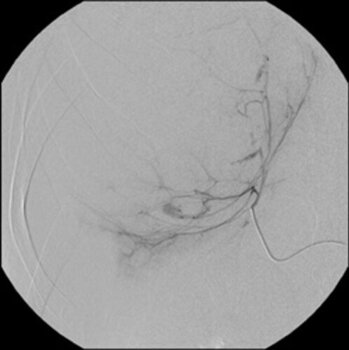

Digitale Subtraktionsangiografie: Superselektive Sondierung und Darstellung der mutliplen Blutungsherde. Die Leberarterien werden durch die zystischen Metastasen ausgespannt.